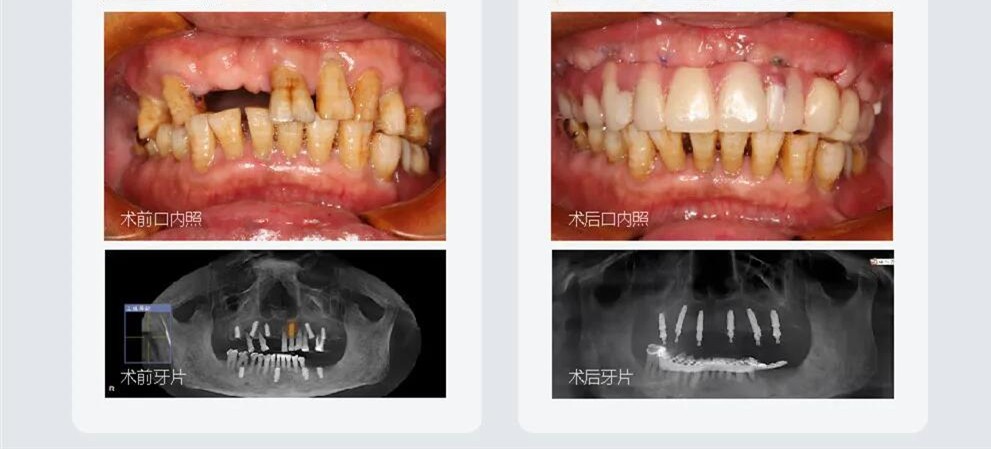

我之前的牙齒有點黃,牙齒之間的間隙也有點大,我向醫(yī)生扒拉了一下我的需求,醫(yī)生給我說烤瓷牙和全瓷牙都可以達到同樣的效果,但是烤瓷牙磨牙太多,還是瓷貼面比較適合我。

貼的時候大約花了40多分鐘,感覺醫(yī)生真的很專業(yè),又是幫我清潔牙縫、試戴、又是貼膠的......看到我做完牙齒貼面后的樣子,感覺一切都值了,真后悔沒有早點來。

瓷貼面修復(fù)后完全可以正常進食滴,并且不會給自己健康的牙齒帶來損傷,由于貼面是超薄的,口內(nèi)也不會有異物感。

在成都做完瓷貼面后的樣子